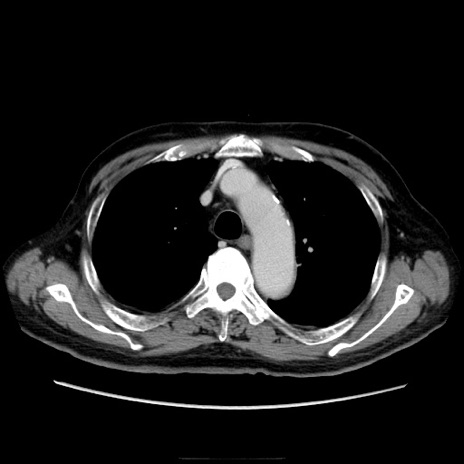

症例21(横断像)

【症例】70歳代男性

【主訴】腹痛

【現病歴】肝硬変・肝細胞癌にてかかりつけの方。約9時間前に食後より腹痛出現。症状が徐々に増悪し、嘔吐出現したため来院。

【既往歴】肝硬変、肝細胞癌(RFA、TACE後)

【身体所見】意識清明、表情苦悶様、BT 36℃、BP 129/78mmHg、P 88bpm、SpO2 97%(RA)、右上腹部から心窩部にかけて圧痛あり、反跳痛なし、筋性防御あり。

【データ】WBC 5800、CRP 0.16